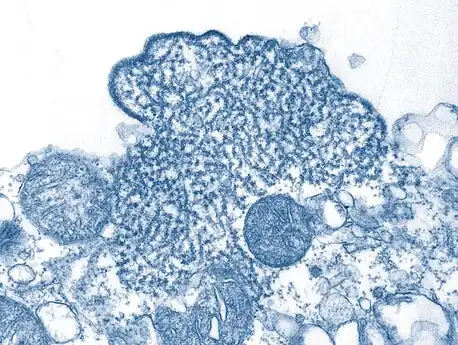

| False-color electron micrograph showing a Nipah virus particle (purple) by an infected Vero cell (brown) | |

Transmission electron micrograph of mature extracellular Nipah Virus particles (yellow) near the periphery of an infected VERO cell -

Nipah virus particles -

Transmission electron micrograph depicted a number of Nipah virus virions